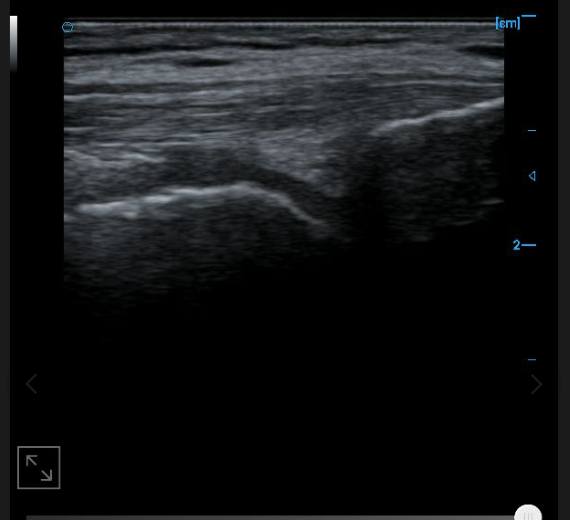

B-image of quadriceps tendon